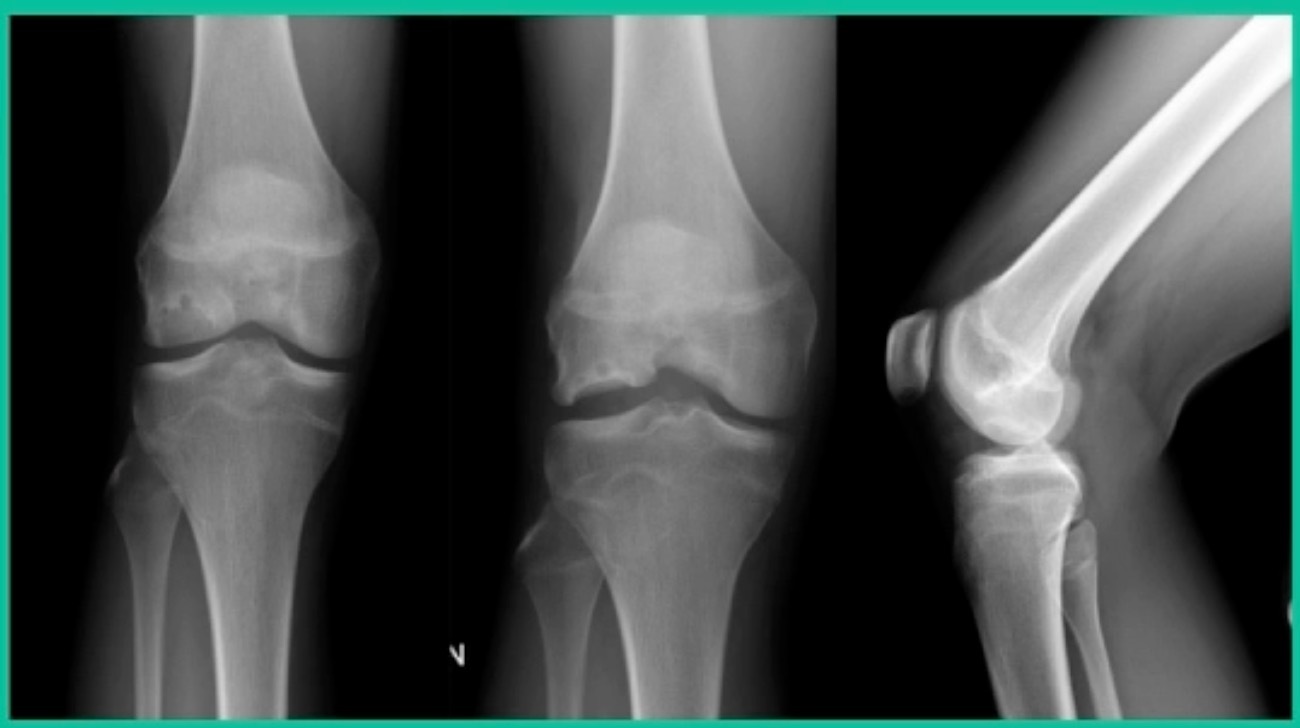

Now, we’ll shift to the adult. This is a 27-year-old. Right knee swelling, activity-related, and classic failed nonsurgical treatment on the lateral side of the knee.

This will probably be fixed. It’s a big piece and we’ll try to preserve it. The literature shows that preservation does pretty well. In this instance, there’s very little bone. It’s somewhat dystrophic, not very encouraging in my mind.

We removed it, and you say, “Well, this is terrible.” Lateral side, how is he going to do? Interestingly, the natural history does not suggest that that person will do badly. Probably the worst ones are going to be the ones who fall off to the side into the trochlea and lateral meniscus.

43-Year-Old, symptomatic medial femoral condyle.

D1 football player formally, affecting ADLs. For this one, I initially just wanted to watch it. This looks pretty small when he came in. Let’s see what happens. Six months later, this is where he progressed to.